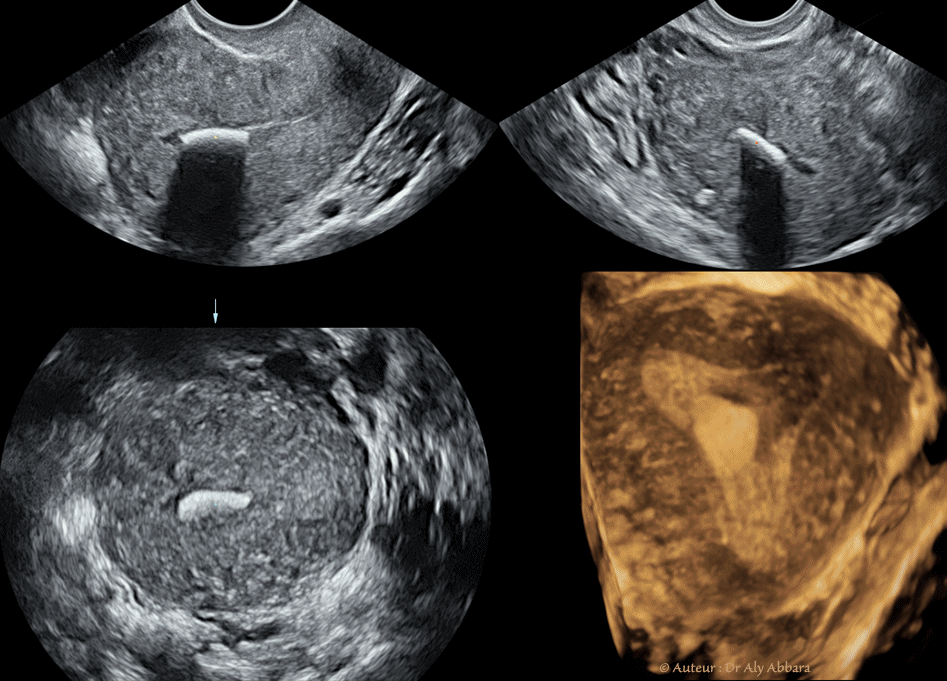

• Utérus : images échographiques, hystéroscopiques et cliniques montrant la présence, dans la cavité utérine, d'un corps étranger de (14.2 x 12 mm de grands axes et de 1 à 1,5 mm d'épaisseur) flottant librement (changeant d'emplacement au cours des échographies successives) :

• Il s'agit d'un corps aplati, légèrement incurvé, de contour irrégulier, hexagone et hyperéchogène laissant apparaître dernier lui une forte cône d'ombre.

• A l'hystéroscopie ce corps étranger flottait librement dans la cavité utérine, sans aucun point d'implantation dans l'endomètre.